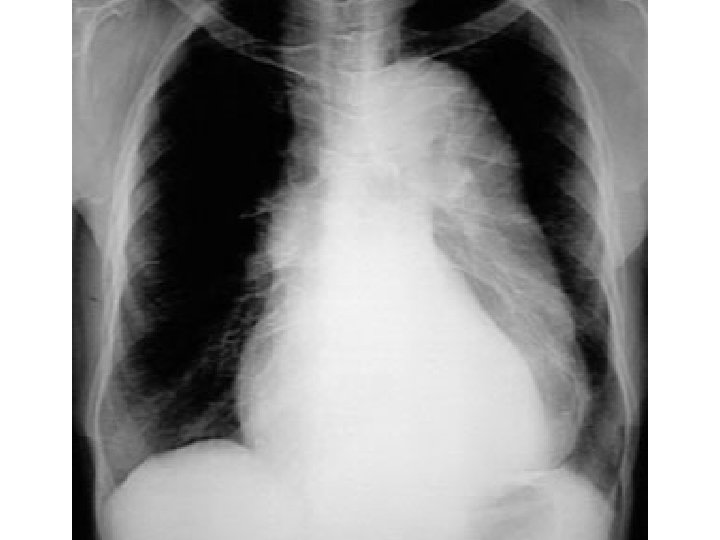

Pulmonary edema

Bilateral Diffuse Alveolar